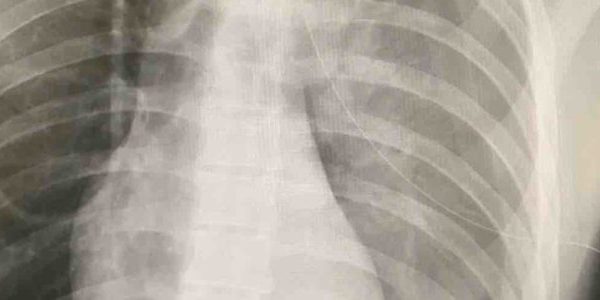

The OMU is equipped with cutting-edge technology, including limited laboratory services, point-of-care ultrasound, and in certain situations, x-ray capabilities. Along with our mobile fleet, OMU allows CrowdRx medical teams to provide rapid, high-quality care to event attendees, no matter where they are on the event grounds. The unit is staffed by experienced medical professionals who are trained to handle any medical emergency that may arise.